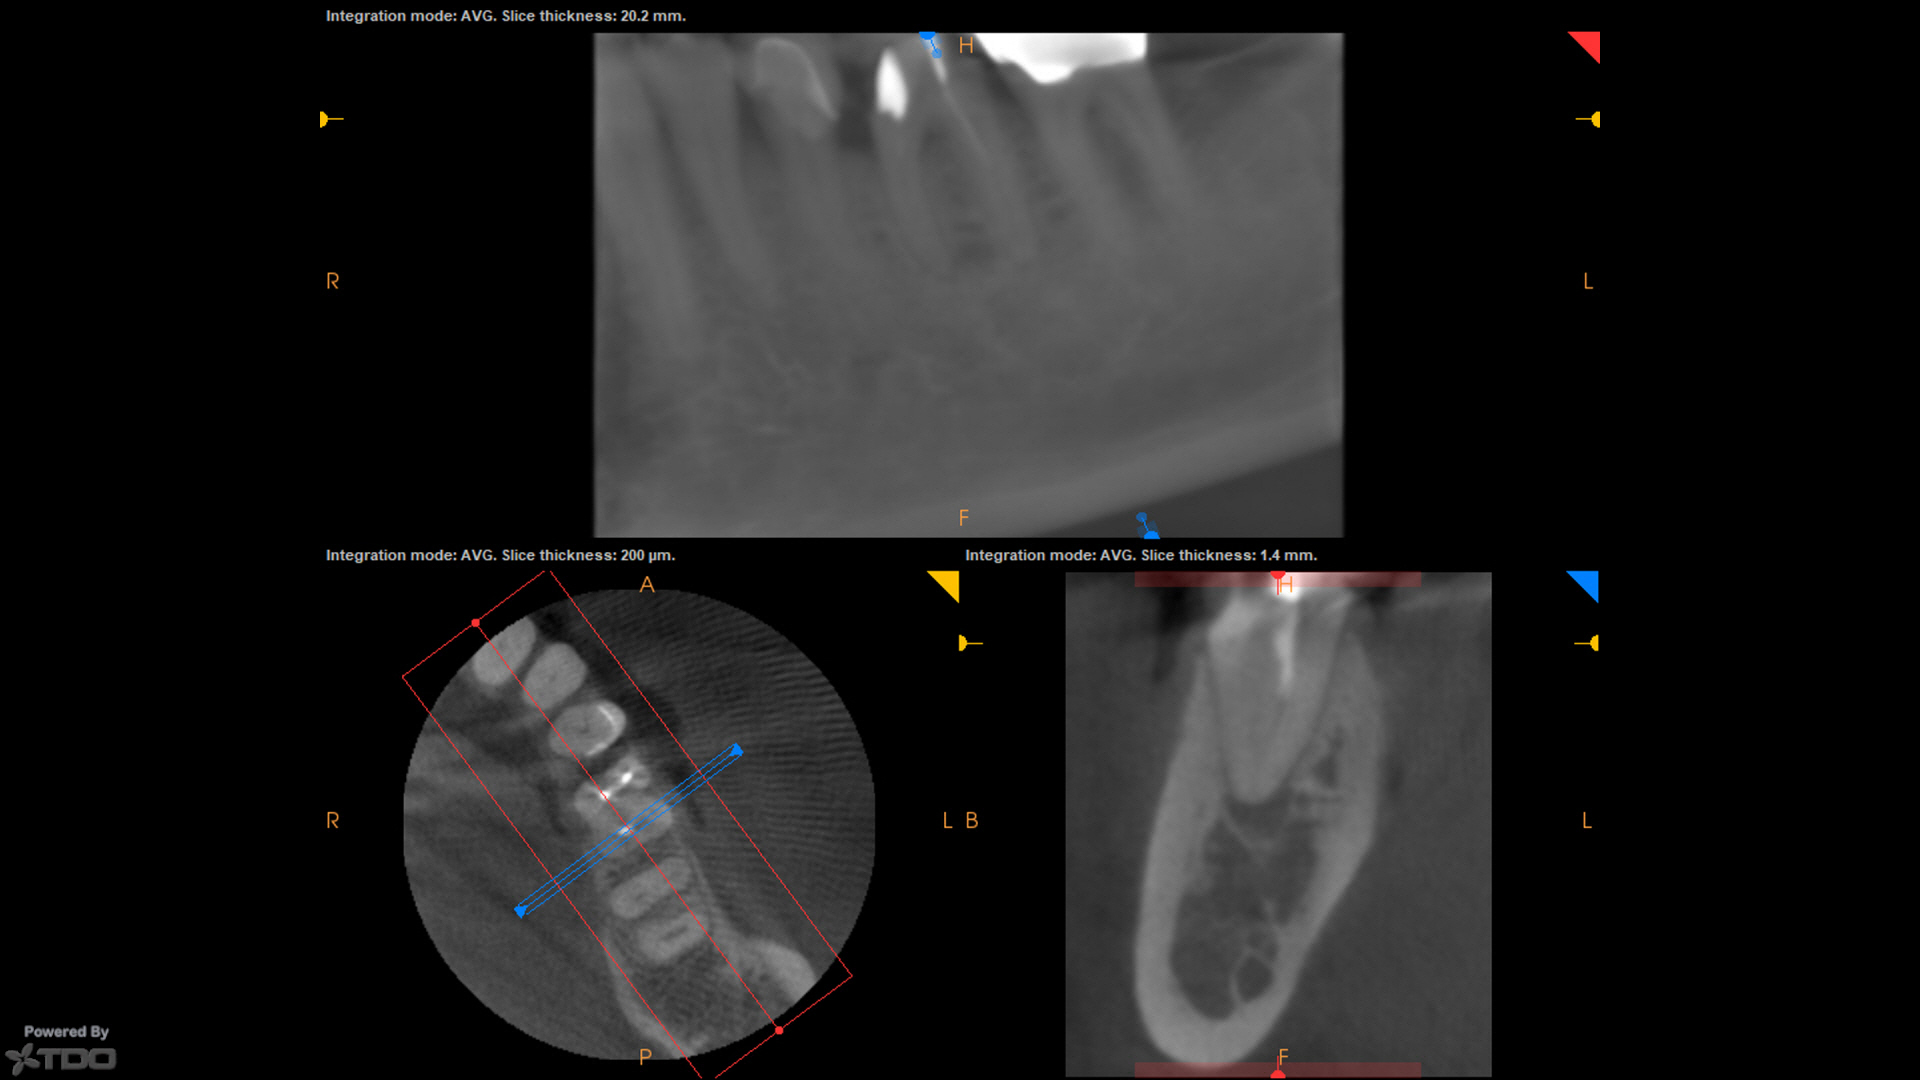

Temporary was left off with hygiene instructions. Tissue was healing well at 1wk, and was perfect today at 1mo complete (not shown). CBCT at the start visit suggested a missed DB, which was addressed at the complete visit today.